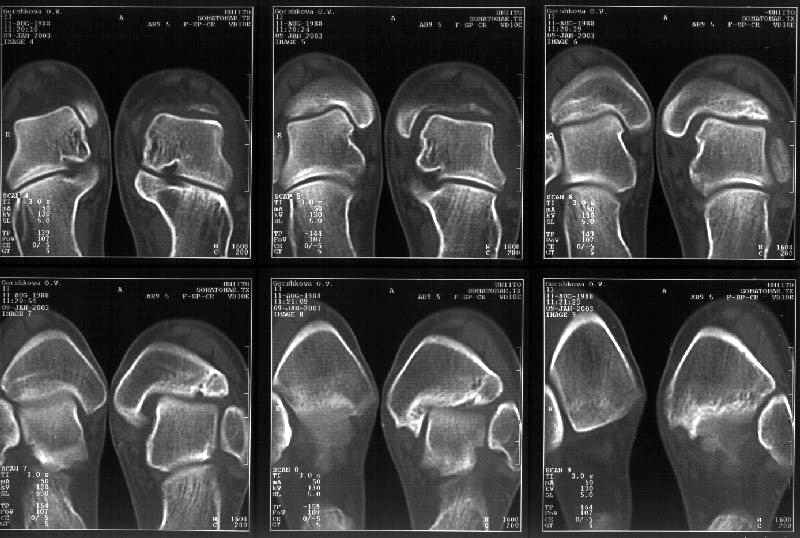

На следующий день пациентке сделали КТ. Может быть, после просмотра картинки будут другие предложения? Не убрать ли ве-таки этот фрагмент

позади внутренней лодыжки, который оттесняет таран кнаружи?

Думаю, КТ прочитан не верно. Задняя часть медиального маллеола, в сущности уже часть заднего маллеола стоит на месте и трогать её не следует. Передняя часть маллеола на 3-4 мм удалена от тарана. Сравните с пространством между

латеральным маллеолом и тараном. В норме все три должны быть одинаковы: между тараном и латеральным, задним и медиальным. Это главное условие устойчивого сидения тарана в голеностопном суставе.

Все-таки она как раз была была отколота и вместе с тараном смещена латерально.

Внутренняя лодыжка не была сломана, она как была на своем месте, так там и находится. Это таран от нее отдавлен кнаружи смщенным в его сторону фрагментом позади внутренней лодыжки. За счет чего и есть проявления нестабильности связок.

Здесь 4 среза, начиная от основания лодыжки и проксимальнее. Где, по Вашему мнению, проходит линия перелома, отделяющая переднюю часть внутренней лодыжки от большеберцовой кости? Заранее спасибо.

Я пометил линию перелома черной линией.

К сожалению на последних присланных срезах КТ нет более низкого, через таран, среза, который был на прежнем майле. На XR я попытался показать

стержень внутри сустава и то как он раскрывает пространство между тараном и мед. малеолом.